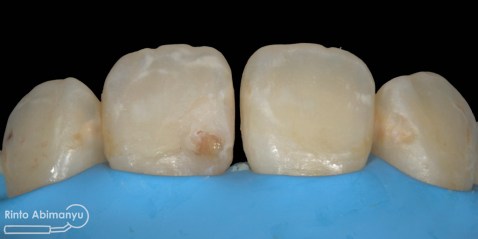

Pada pemeriksaan intra oral terlihat gigi 23 dan 24 mengalami karies dan cukup banyak sisa makanan terjebak disana…

Pertama saya lakukan anestesi infiltrasi dan kemudian memasang rubber dam untuk isolasi daerah kerja, dilanjutkan pembersihan karies dan pembukaan kamar pulpa.. Pada kasus ini pengerjaan dilakukan langsung pada dua gigi…